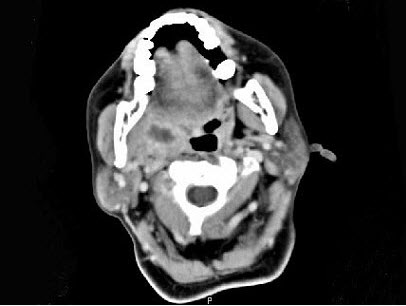

女,52岁,咽喉部疼痛半个月,伴低热,CT如图所示,可能诊断为()。

A:咽旁脓肿

B:咽部神经鞘瘤

C:鼻咽血管纤维瘤

D:咽旁淋巴瘤

E:咽旁转移癌